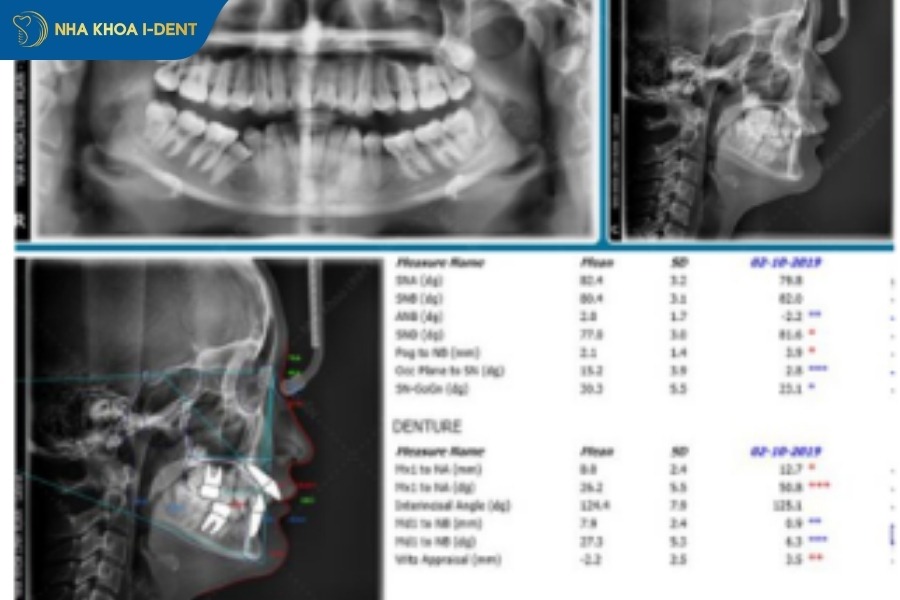

3.2. Thu thập dữ liệu & phân tích hình ảnh số

Để quá trình niềng răng diễn ra thuận lợi, bác sĩ sẽ tiến hành thăm khám tổng quát và chụp phim X-quang để đánh giá tình trạng răng của bệnh nhân như răng bị thưa, hô (vẩu), móm, răng khấp khểnh hay lệch khớp cắn…

Bên cạnh đó, tùy vào mục đích thăm khám mà bác sĩ có thể chỉ định một số kỹ thuật chụp phim khác nhằm giúp việc thu thập dữ liệu tình trạng răng, xương hàm đạt kết quả chuẩn xác, chẳng hạn:

- Chụp phim Ceph/Pan (CT Cone Beam 3D), scan trong miệng 3D bằng máy iTero Lumia.

- Chụp phim Cephalo và Pano xem toàn cảnh các răng, xương hàm.

- Chụp phim quanh chóp khi cần khảo sát tình trạng răng nhất định, chụp CBCT khảo sát những cấu trúc và răng mọc bất thường như răng dư và răng mọc ngầm.

Toàn bộ dữ liệu trên (bao gồm cả ảnh trong miệng và ngoài mặt) là nền tảng số hóa giúp mô phỏng chính xác tình trạng răng và xương hàm.

3.3. Phân tích khớp cắn và không gian

Bác sĩ đo đạc các chỉ số xương, răng, mô mềm, đánh giá tình trạng chen chúc và lệch đường giữa. Bác sĩ sẽ dự kiến việc nhổ răng (nếu cần) và các can thiệp hỗ trợ như IPR (mài kẽ) hay cắm minivis, đồng thời minh bạch rằng các can thiệp này chỉ áp dụng khi thật sự cần thiết và luôn có phương án thay thế.